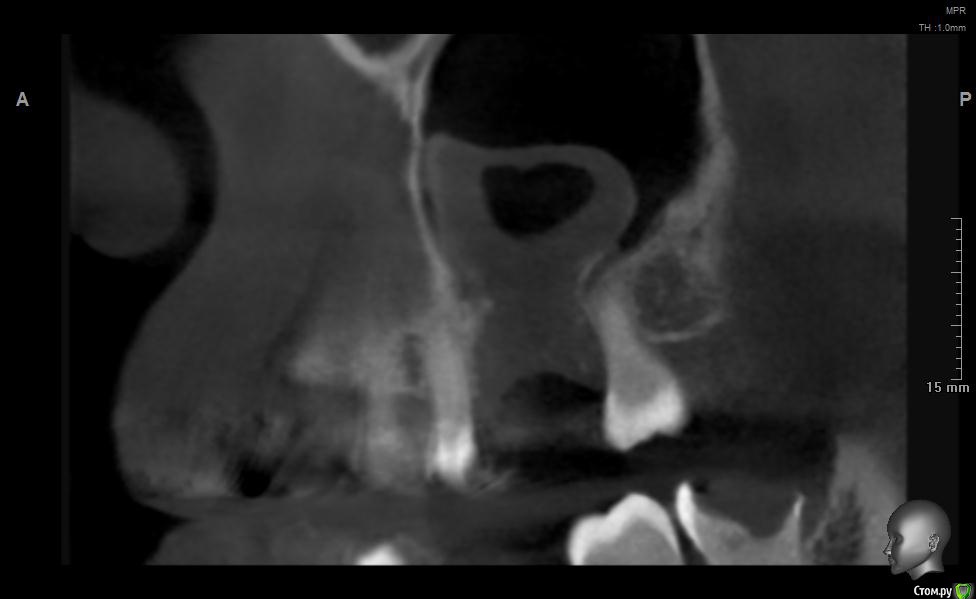

jm3300 Опубликовано 20 мая, 2019 Поделиться Опубликовано 20 мая, 2019 Добрый день. Пациент не мой, причины удаления, а так же о ходе удаления сказать ничего не могу. Известно лишь, что после удаления из лунки получили много зеленоватой жидкости. Удаляли с месяц назад. До сих пор имеется не сильно зияющая дырка. Нужно что то делать или просто ждать пока вторичным затянется. И если имплант планировать- ожидать ли там самостоятельного появления обьема кости? Ссылка на комментарий

L.E.S.I.K. Опубликовано 20 мая, 2019 Поделиться Опубликовано 20 мая, 2019 Я бы сделал ревизию через лунку, убрал оболочку кисты (похоже что она там осталась, или это эпителий врос - не важно) и провел бы закрытие небным лоскутом. При направлении в ЧЛХ есть вероятность, что наведут "разруху"(по Колддвел-Люк) и пациент получит проблему при дальнейшей реабилитации. З.Ы. На данных срезах не видно остиомеатальный комплекс- крайне желательно, чтобы он был не блокирован. 3 Ссылка на комментарий

Irouil Опубликовано 20 мая, 2019 Поделиться Опубликовано 20 мая, 2019 Я бы дождался эпитлизации (2 месяца), потом 2 варианта: В пазуху свистит - первым этапом разобщить, вторым этапом синусить В пазуху не свистит - сразу синусить Судя по наблюдаемой картине, соустье чистое 2 Ссылка на комментарий

Дмитрий М Опубликовано 21 мая, 2019 Поделиться Опубликовано 21 мая, 2019 месяц прошел, уже ничего не дождетесь, кость там не вырастет т.к. уже пошла эпителизация. так и останется не сильно зияющая дырка только вы видите клиническую картину, поэтому вам решать какой вариант лучше выбрать.в любом случае удалять кисту, оболочку, вероятно будет сообщение, которое необходимо закрывать и по ситуации готовиться к обоим вариантам по снимкам это скорее киста, (прослеживается кортикальная по контуру) 1 Ссылка на комментарий

Дмитрий Л. Опубликовано 21 мая, 2019 Поделиться Опубликовано 21 мая, 2019 Там уже есть сообщение с гайморовой. Возможно не функционирующее. Вяло текущий хронический воспалительный процесс. Ждать мало смысла. Если стремиться сделать всё как можно менее инвазивно, можно пойти по такому пути:1. Недельку попромывать соустье антисептиками. Воспаление стихнет. Десны добавится.2. Расскрыться. Аспирировать слизистую слюноотсосом. Кюретаж, всё через лунку. Если функционирующего соустья не было, оно появится.3. Небный лоскут, чтоб ушить соусье. Сосудосуживающие в нос, антибиотики. Ссылка на комментарий

jm3300 Опубликовано 21 мая, 2019 Автор Поделиться Опубликовано 21 мая, 2019 Ну по КТ и клинически сообщения с пазухой нет. Пациента,кроме наличия самой лунки, вообще ничего не беспокоит. Ссылка на комментарий